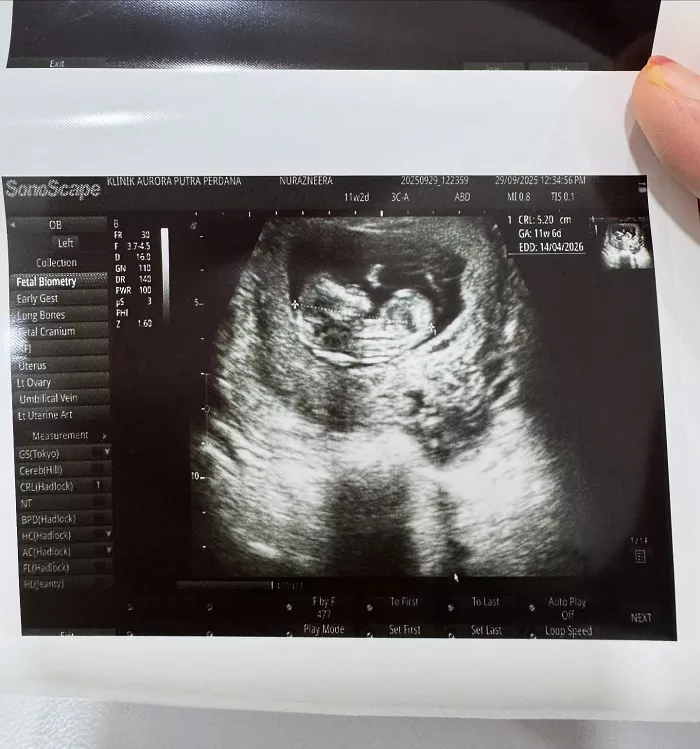

Berita gembira itu dikongsi menerusi hantaran di laman Instagram miliknya, yang memperlihatkan gambar imbasan kehamilan serta buku rekod kesihatan ibu mengandung.

Malah Neera juga memberitahu dirinya sangat bersyukur dengan rezeki yang diberikan oleh Allah dan memaklumkan bahawa kandungannya kini sudah memasuki usia 13 minggu.